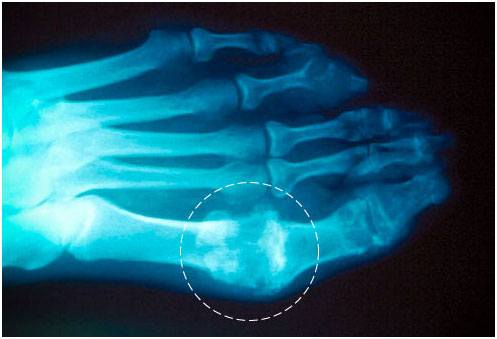

痛风是一种常见且复杂的关节疾病,可导致关节极度疼痛和肿胀。引发痛风的根本原因是体内尿酸水平的升高,造成了尿酸盐(痛风石)在关节和肾脏部位的沉积。